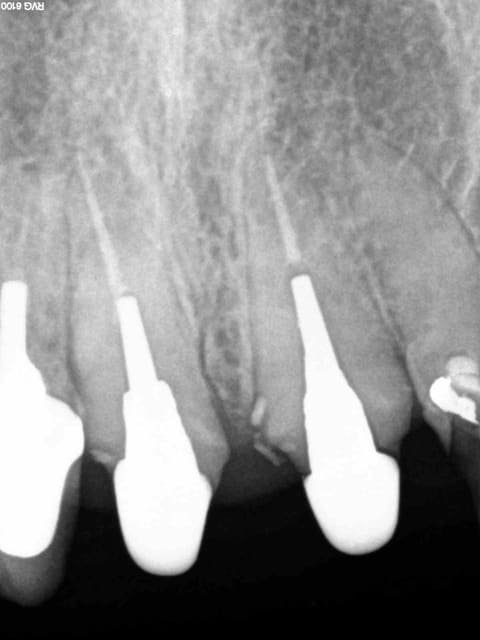

11 21 de la balle crjq1n - Eugenol

Pose 2 ic coiffe 10 mn mxgarl - Eugenol

11 21 endo turbo so1akt - Eugenol